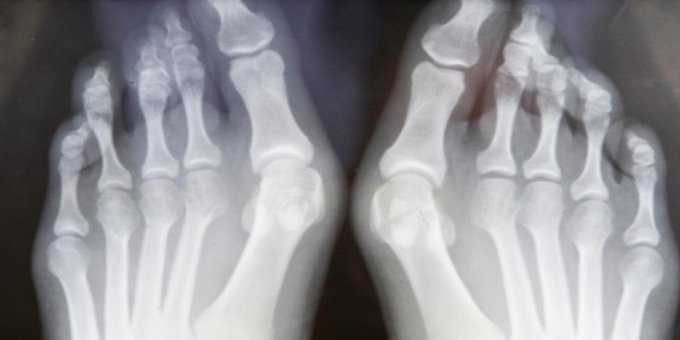

Un juanete es una protuberancia en un dedo que puede provocar dolor. Entérate sobre causas, tratamientos y más aquí ow.ly/YmEU50xkOMw